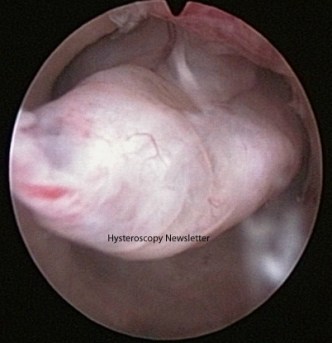

The simplest answer to this clinical question would be a resounding yes. The concern is the possibility of malignancy located in the polyp. However, the presence of cancer cells in endometrial polyps is very rare. Dockerti Ferris in 1944 established diagnostic criteria for adenocarcinoma originated in an endometrial polyp. First, the carcinoma must be limited to a portion of the polyp, second, the base of the polyp should be free of cancer cells and third, the endometrium surrounding the base of the polyp should be normal.

The recommended procedure is hysteroscopy polypectomy and the risk of encountering a malignant lesion should not be the only criteria to value when deciding to offer polypectomy. Therefore, several questions arise when considering a polypectomy: